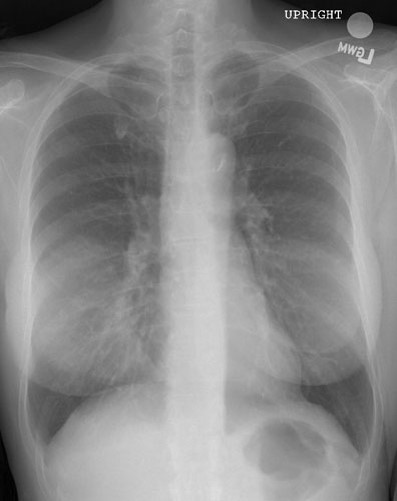

65yo male with DOE and a feeling that he “can’t catch my breath”

View:

DX:

View: PA

DX: CHF exacerbation leading to pulmonary edema